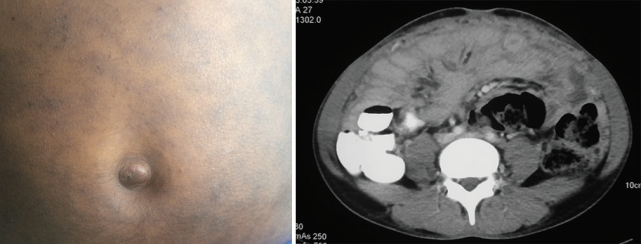

图片

腹腔结核感染与 Sister Mary Joseph’s nodule(图片来自文献 [23])